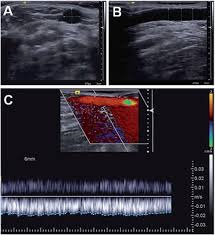

Duplication Of The Median Cubital Vein Case Report With Commentaries On Clinical Significance Sciencedirect

Duplication Of The Median Cubital Vein Case Report With Commentaries On Clinical Significance Sciencedirect from ars.els-cdn.com